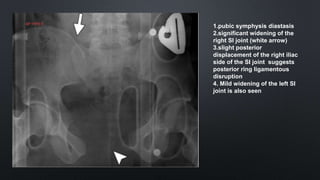

1.pubic symphysis diastasis

2.significant widening of the

right SI joint (white arrow)

3.slight posterior

displacement of the right iliac

side of the SI joint suggests

posterior ring ligamentous

disruption

4. Mild widening of the left SI

joint is also seen